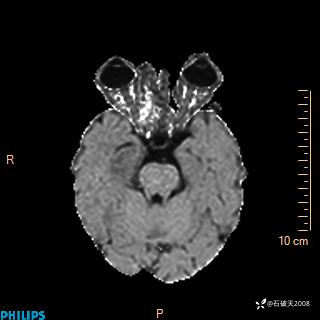

颅内占位,影像征象不是很丰富,有病理

hyy838 推荐女 62岁 主 诉:头晕12小时,加重1小时。

现病史:患者于12小时前无明显诱因出现头晕,呈持续性,无天旋地转及行走不稳,伴恶心、呕吐,呕吐共5次,呕吐物为胃内容物(具体性质不详),无胸闷、胸痛、心慌,无腹痛、腹泻,无咳嗽、咳痰,无发热、意识不清、肢体抽搐及大小便失禁等,1小时前患者上述症状加重,未诊疗,为求进一步治疗急自行来我院,门诊以“头晕待查”为诊断收入我科,发病来,神志清,精神差,饮食、睡眠差,大小便正常,体重未见明显下降。

DWI